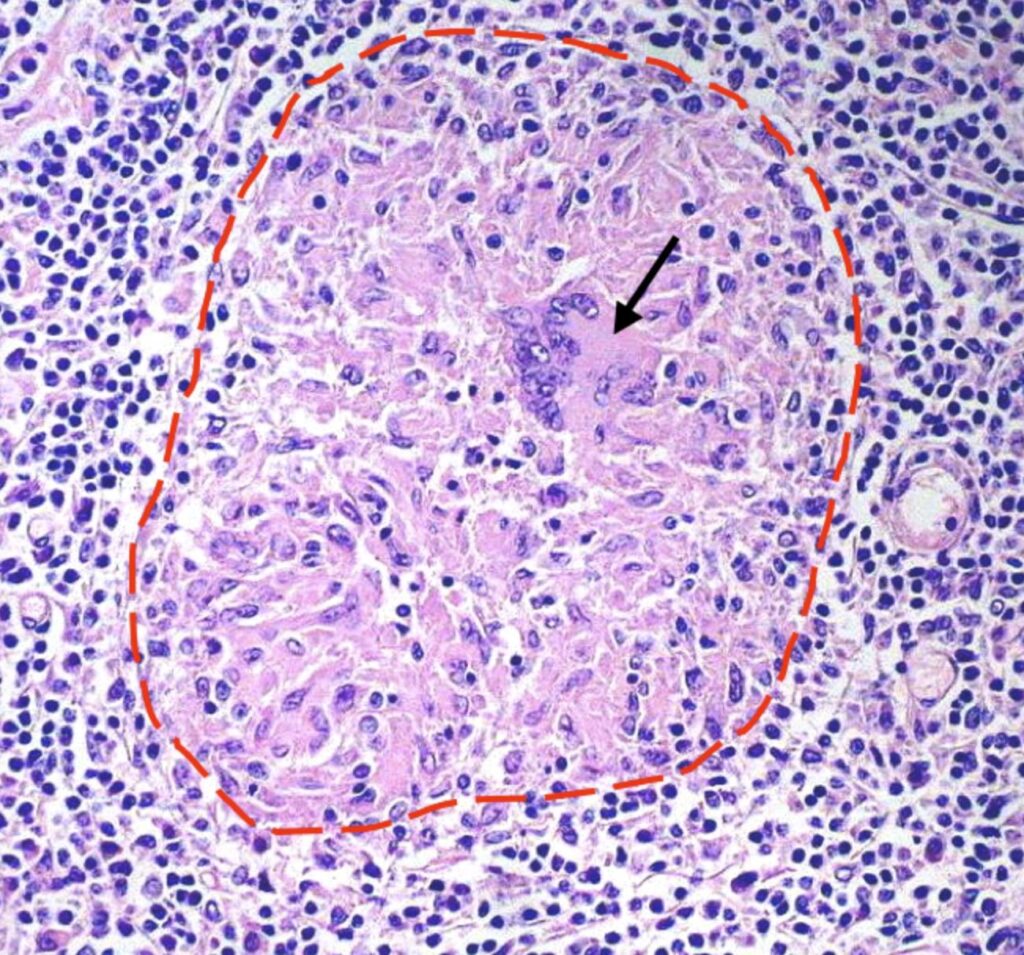

Som reaktion på den ukontrollerede infektion i makrofagerne, iværksætter immunsystemet en mere organiseret forsvarsstrategi. Det samler forskellige typer immunceller, herunder flere makrofager, T-lymfocytter og B-lymfocytter, omkring de inficerede celler. Denne organiserede struktur kaldes et granulom. Granulomet er kendetegnet for tuberkulose og tjener et dobbelt formål. For det første fungerer det som en fysisk barriere, der inddæmmer bakterierne og forhindrer dem i at sprede sig til resten af kroppen. For det andet skaber det et lokalt mikromiljø, hvor immuncellerne kan koordinere deres angreb på Mtb.

I de fleste tilfælde (omkring 90% af infektionerne) lykkes det for immunsystemet at kontrollere infektionen inden i disse granulomer. Bakterierne bliver ikke elimineret, men holdes i skak i en dvaletilstand. Dette er kendt som latent tuberkuloseinfektion (LTBI). Personen er ikke syg, har ingen symptomer og kan ikke smitte andre. Granulomet kan dog også blive bakteriens redning. Inden i granulomet kan forholdene blive iltfattige (hypoksiske) og næringsfattige, hvilket netop er de signaler, der får Mtb til at gå i dvale og blive resistent over for behandling.

Forskellige typer granulomer

Granulomer er ikke statiske, men kan udvikle sig over tid, især under aktiv sygdom:

- Solide granulomer: Typiske for latent TB. Velorganiserede strukturer med få, dvalende bakterier.

- Nekrotiske granulomer: Centrum af granulomet begynder at dø (nekrose), hvilket skaber en osteagtig masse. Bakterierne kan begynde at formere sig i dette miljø.

- Kaseøse granulomer (kaviteter): Det nekrotiske centrum bliver flydende (kaseøst), og granulomet kan briste ind i en luftvej. Dette frigiver enorme mængder bakterier, som kan hostes op og smitte andre. Patienten har nu aktiv, smitsom tuberkulose, og der opstår hulrum (kaviteter) i lungevævet.